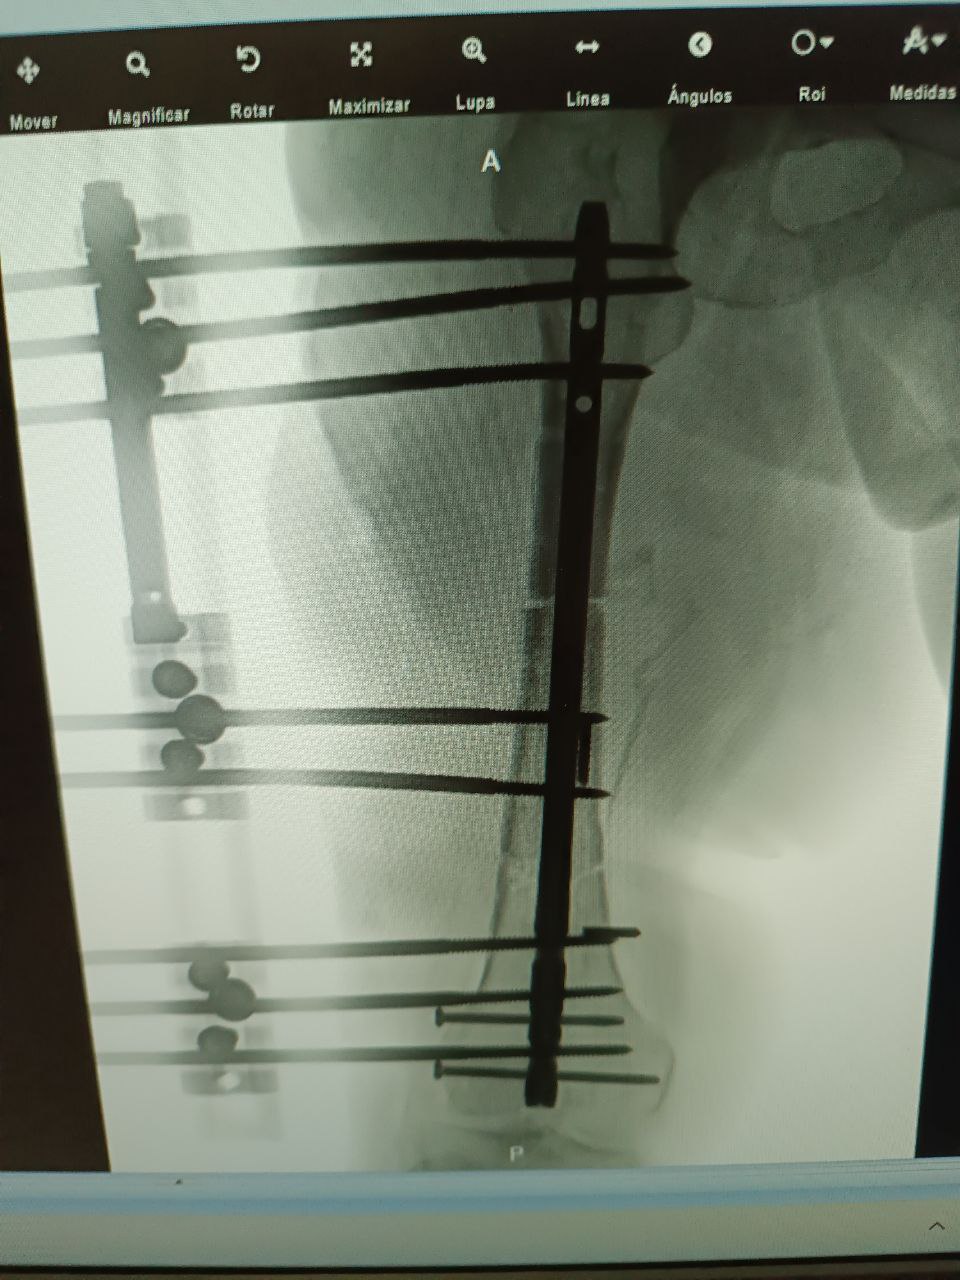

Corrección de Deformidades con Ilizarov

Corrección de deformidades óseas mediante el método Ilizarov y transporte óseo. Técnica de referencia mundial para casos complejos que otros no se atreven a tratar.

- Método Ilizarov

- Transporte óseo

- Corrección angular

Cirugía Reconstructiva

Recuperación exitosa tras cirugía de alta complejidad

Corrección de Deformidades Complejas

Soporte pélvico y fijación de fracturas complejas